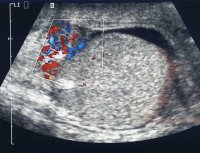

In der Angiodynographie vermehrte Farbimpulse im Nebenhodenbereich (Abbildung 3), evtl. AUR: bei Verdacht auf Obstruktion der Harnwege mit Harnwegsinfekt